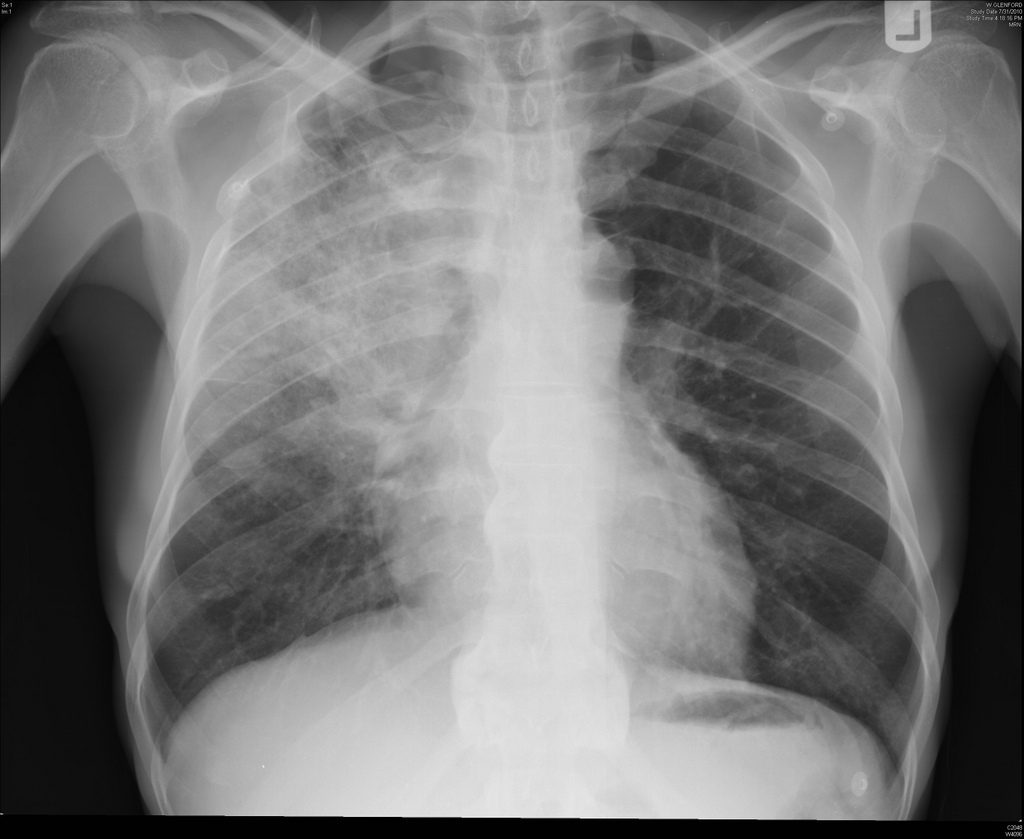

A pneumonia é uma doença inflamatória aguda que acomete os pulmões e pode ser provocada por bactérias, vírus, fungos ou pela inalação de produtos tóxicos. O Streptococcus pneumoniae é o agente causador em 60% dos casos. As principais manifestações clínicas da doença são tosse com produção de expectoração; dor torácica, que piora com os movimentos respiratórios; mal-estar geral; falta de ar e febre.

Foto; EBC